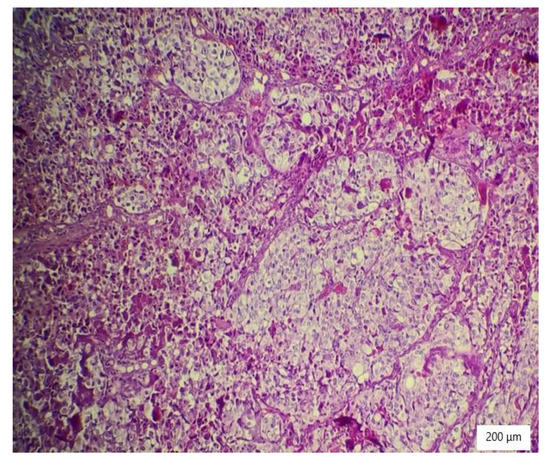

The microscopic analysis of the cervical mass biopsy showed the presence of the following morphological aspects: mixed architecture with solid and tubulocystic patterned areas; mainly composed of nests of cells with clear or eosinophilic cytoplasm (intracytoplasmic glycogen); and prominent hyperchromatic nuclei, some with round nucleoli and high mitotic activity (16/10 HPF) (Figure 2, Figure 3 and Figure 4). Additionally, we noted abundant inflammatory infiltrate that was mainly made up of the lymphocytes and plasmacytes present in the hyalinized stroma, and this was determined to be associated with the area of necrosis. Periodic acid–Schiff staining was strongly positive in the cytoplasm, consistent with glycogen (Figure 5). Immunohistochemical staining showed a diffuse positive reaction for CK AE1/AE3, PAX8, and AMACR; rare cells showed CEA-positive expression; and there was a negative reaction for p63, CD30, OCT4, ER, SALL4, synaptophysin, CD56, and p16, which were focally positive in tumor cells (Figure 6, Figure 7, Figure 8, Figure 9, Figure 10 and Figure 11). The histological diagnosis was HPV-negative clear cell adenocarcinoma of the uterine cervix.

Figure 3. Tubulocystic pattern of tumor cells with clear cytoplasm, inflammatory infiltrate, necrosis, and hemorrhagic areas (HE ×100).